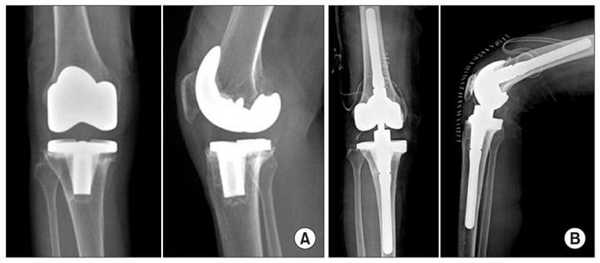

- тотальная операция (полная) - меняется весь коленный сустав, он удаляется полностью, а на его место имплантируется эндопротез;

Неполные имплантаты, устанавливаемые при частичной замене, имеют короткий срок эксплуатации. Такие модели вырабатываются в 2 раза быстрее, чем тотальные конструкции, при этом их потенциал прочности не рассчитан на высокой степени физические нагрузки. Преимущества частичного протезирования состоят в том, что замещается имплантатом только определенная часть сочленения, остальная область остается нетронутой. Таким образом, щадящее вмешательство позволяет сократить сроки реабилитации и перенести восстановительный период относительно легко.

Две техники операции у одного пациента.

Вы уже знаете, что бывает полное и частичное эндопротезирование коленного сустава, где в первом случае лечение подразумевает полноценную замену суставных поверхностей, а во втором - имплантацию поврежденного участка одного из мыщелков. Соответственно, протезы классифицируются на тотальные, одномыщелковые и ревизионные для замены импланта.

Сравнение двух типов операций.

С каждой последующей операции статистика успешности ниже. Импланты при этом становятся все более громоздкими.

Одномыщелковое протезирование подразумевает срок службы небиологического устройства максимум 7 лет. Тотальное замещение предусматривает время службы вживленного механизма от 15 лет. Ревизионное переносится сложнее, а риск инфекции и других негативных явлений почти в 2 раза выше, чем после первичной операции.